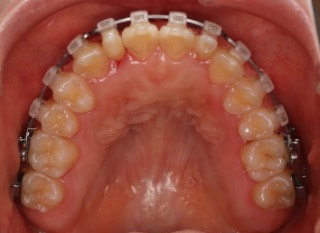

治療開始から25ヶ月後